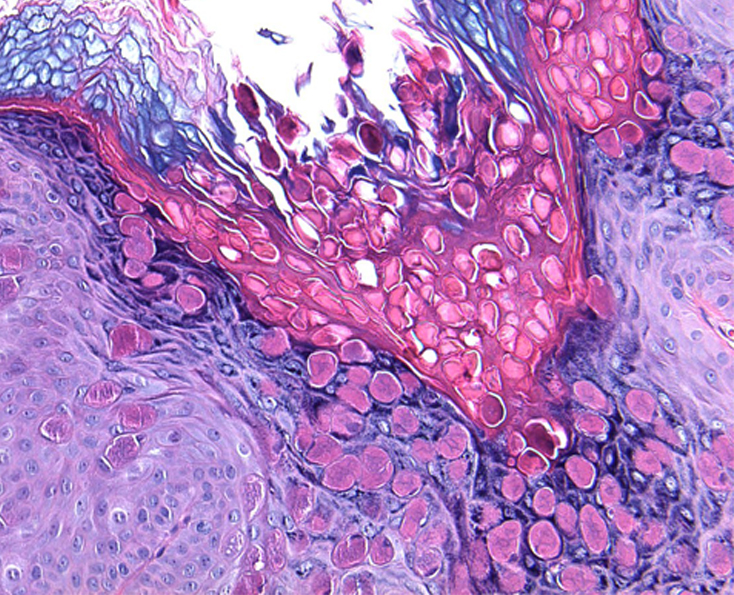

Клинические проявления неинфекционных заболеваний кожи при поражении аногенитальной области в целом не отличаются от таковых другой локализации. Однако целый ряд особенностей пораженной области – разная степень кератинизации эпителия, хорошая васкуляризация, окклюзия и мацерация кожным салом, потом и вагинальным отделяемым, высокий рH кожи (результат расщепления бактериальными уреазами мочевой кислоты с образованием аммиака), трение – нередко приводят к изменениям их клинической картины. Это существенно затрудняет распознавание заболеваний гениталий и перианальной области. Значительное сходство субъективной симптоматики и клинических проявлений дерматозы аногенитальной области имеют с инфекционными, а также предраковыми заболеваниями данной локализации, что нередко является одной из причин поздней диагностики дерматозов и предраков. Ситуация усложняется различием классификаций и терминов, используемых разными клиницистами

(акушерами-гинекологами, урологами,дерматологами) и морфологами, что приводит к непониманию и затрудняет преемственность (комплексный подход) в ведении этих пациентов.

Лечение дерматозов аногенитальной локализации нередко представляет сложную задачу и требует междисциплинарного подхода. Основные подходы к лечению дерматозов данной локализации включают восстановление кожного барьера, назначение противовоспалительных препаратов, в частности топических глюкокортикостероидов и/или топических ингибиторов кальциневрина, реже – системных глюкокортикостероидов, ретиноидов, гидроксихлорохина или дапсона, ослабление субъективной симптоматики, профилактику и лечение вторичной инфекции. Отсутствие эффекта от противовоспалительной терапии требует исключения предраковых заболеваний вульвы и является показанием для диагностической биопсии.